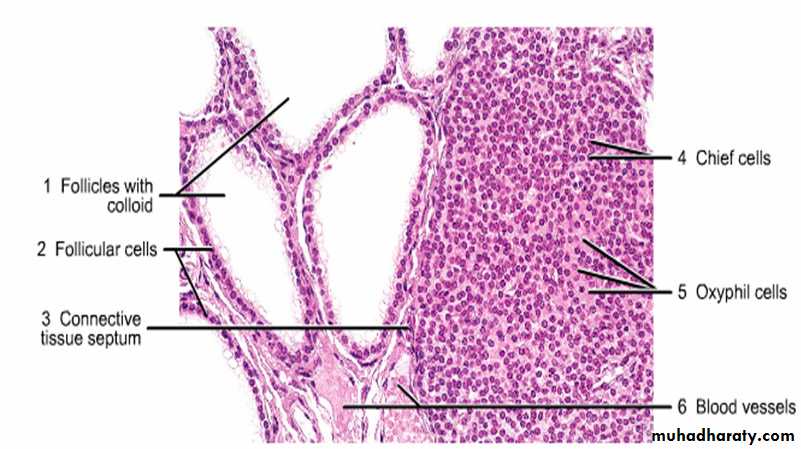

Thyroid gland (general view) . Stain H&E. Low magnification .

Thyroid gland follicles. Stain: H&E. High magnification.